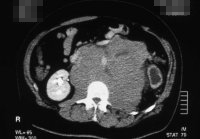

Die ausgedehnte retroperitoneale LK-Metastasierung (Bulky disease) eines Hodentumors (Embryonalkarzinom und Seminom) mit Ummauerung der großen Gefäße (Aorta und Vena cava) sowie des linksseitigen Nierengefäßstieles führte bei dem jungen Mann zu einer vasculär bedingten Schrumpfung der linken Niere (Abbildung 18a,e) (

s. Tumoren/Hoden).

In der Sonographie fand sich eine kleine Niere links bei unauffälliger rechter Niere (Abbildung 18b).